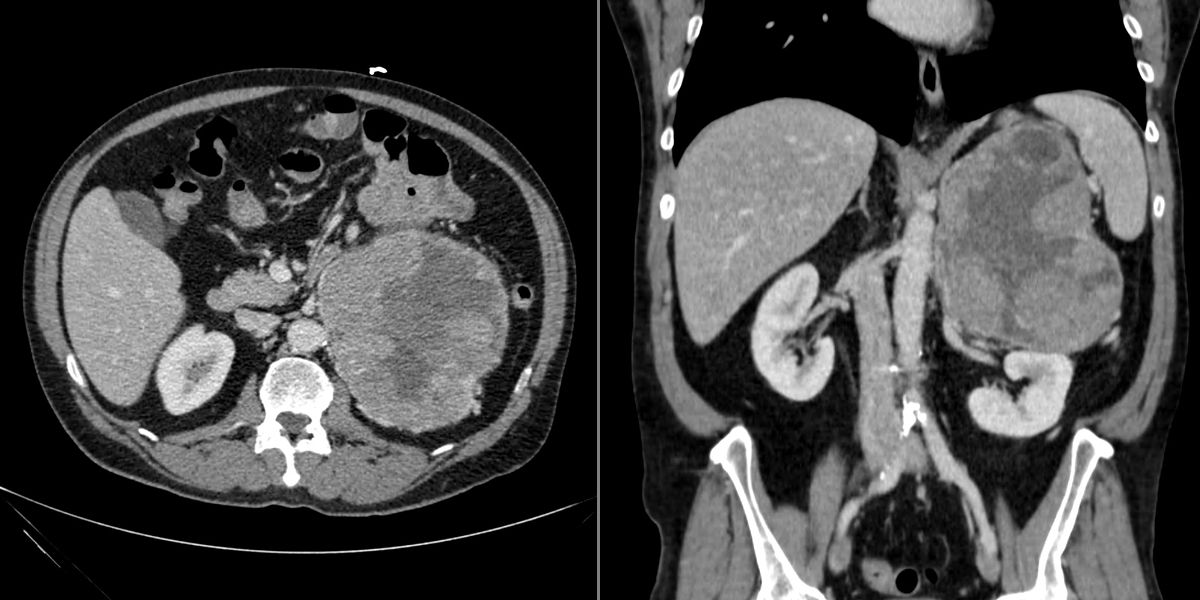

A 56-year-old woman presents with abdominal fullness and virilization. Axial and coronal images from a CT scan of her abdomen are shown below. What is your diagnosis?

A 56-year-old woman presents with abdominal fullness and virilization. Axial and coronal images from a CT scan of her abdomen are shown below.

What is your diagnosis?